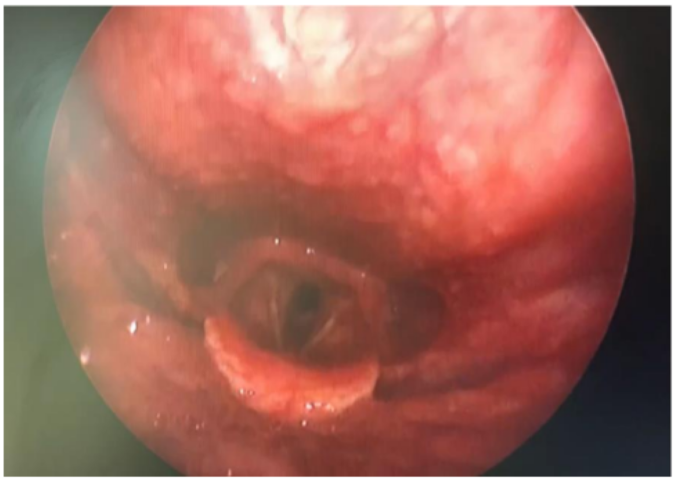

Image 5: Post operative rigid telescopy of larynx showing an improved tracheal airway

She was monitored post operatively in cardio-thoracic ICU for a day and then shifted to the ENT ward. Her vitals were stable, there was no stridor and she had no complaints of breathing difficulty. She was discharged and advised to continue steroid inhaler for 1 week.

On subsequent follow-up after one week, she was asymptomatic with no stridor or breathlessness on exertion.

The histopathology report was reported as granulation tissue from trachea with no evidence of malignancy.